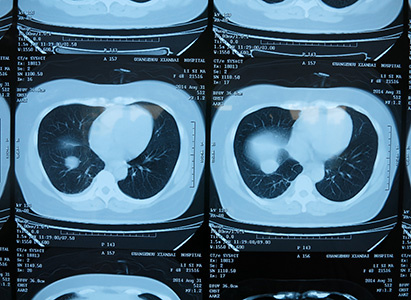

So far, Risma Idawaty Saragih have underwent four times of interventional therapy, one time of radiotherapy, and one biological immunotherapy. As all those treatments were minimally invasive treatments, Risma Idawaty Saragih did not feel much discomfort. According to her, the doctor who performed the interventional therapy for her was very experienced: the trauma was very small and there were few side effects. She did not lose much hair, no vomit, her appetite was very good, and she even gained 3kg after the treatment. The curative effect was also very good. In the admission diagnosis it said there were recurrences in liver and lungs, but after treatment tumors in the liver disappeared, only some were remained in the lungs. CT results showed that the bladder distorted due to pressing of tumors has also restored to normal shape, so the abdominal pain which had long plagued her disappeared. As a result, her defecation also returned to normal and the sleep was acceptable.